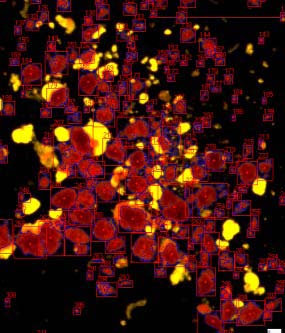

ICC4-230是胰島細胞自動化計數儀器:

2. 全新的暗場照明提高了小顆粒檢測、圖像分割的能力,并且可以計數純化的未染色樣本;

細胞自動檢測,SNR掃過RGB范圍后的閾值

先進的自適應分區算法